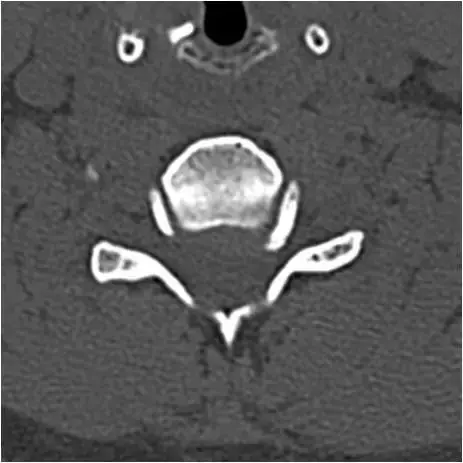

图23:下颈椎的轴向截面。广泛的骨赘形成和右钩椎关节肥大。硬膜囊颈髓的前部受压。确定脊柱狭窄。

图24:下颈椎的轴向截面。骨窗。与图像23相同的患者和相同水平。广泛的骨赘形成和右钩椎关节肥大。硬膜囊颈髓的前部受压。确定脊柱狭窄。